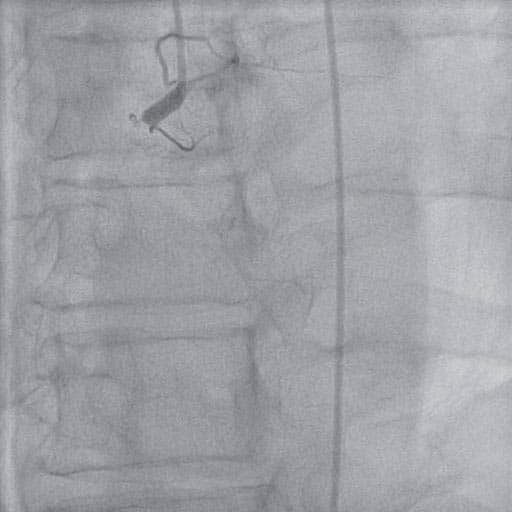

Figure 1A. Proximal occlusion of RCA.

Figure 1B. RCA – high amount of thrombotic material.

Figure 1C. Final PCI result on RCA.

Case report: We present the case of a male patient, 80 years old, hypertensive, dyslipidaemic, with a history of inferior myocardial infarction and angioplasty with 2 BMS on the right coronary artery (2012), who presented an episode of loss of consciousness, followed by motor deficit of the lower limbs and dysarthria. He was admitted to neurology and a head CT scan was performed, this showed no acute hemorrhagic lesions. The myocardial biomarkers were raised and the electrocardiography (EKG) showed ST segment elevation in the inferior leads. The patient was diagnosed with inferior ST-segment elevation myocardial infarction (STEMI) and was referred to our clinic for further investigations and treatment. At admission, the patient accused no angina or dyspnea, but was somnolent and had crural motor defi cit. The myocardial necrosis markers were elevated and the EKG showed persistent ST segment elevation in DII, DIII, aVF with negative T waves and Q waves and ST segment depression in the reciprocal leads. Echocardiography showed a moderately depressed ejection fraction (EF=35%) with akinesia of the inferior wall and apical half of the interventicular septum and a moderate aortic stenosis. The patient underwent urgent coronarography, which revealed right coronary artery (RCA) proximal occlusion and 70% calcified stenosis of the left anterior coronary artery. We decided for emergency percutaneos coronary intervention (PCI) on the right coronary artery. After the occlusion was passed with a hydrophilic guidewire, we predilatated with a semicompliant balloon,but no fl ow was obtained due to the high amount of thrombotic material. We performed multiple thromboaspiration passages, with the extraction of numerous thrombi and vessel repermeabilization was obtained. A long drug eluting stent was implanted with a very good angiographic result, TIMI 3 fl ow to distal RCA. During the hospitalization, the patient’s evolution was unfavorable. He started having episodes of atrial fibrillation and non sustained ventricular tachycardia which were successfully treated with amiodarone. On the third day after admission, the patient became agitated and disoriented; the neurological motor deficit was accentuated. A second CT scan was performed which revealed subacute ischemic stroke in the right posterior junctional territory and a chronic subdural hematoma with a minimal shift of the midline structures contralateral. The patient was transferred to a